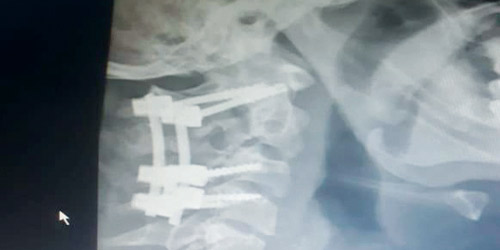

تمكن فريق جراحة العمود الفقري بالمستشفى السعودي الألماني بالرياض، مكون من استشاري جراحة العمود الفقري د.إبراهيم العسيري ود.حازم فريد بفضل الله من إنقاذ حياة مواطن سعودي يبلغ من العمر عشرين عاماً وذلك بعد أن أجريت له جراحة وصفت بأنها في منتهي الدقة والصعوبة، تمثلت في تثبيت كسر غير مستقر بالفقرة العنقية الثانية، نتج إثر حادث مروري تعرض له المواطن السعودي، الذي معه كان يخشي على حياته، حيث تكمن الخطورة في احتمالية إصابة أعلى جزء من الحبل الشوكي لوجود الكسر أعلى الفقرات العنقية وأسفل الجمجمة مباشرة وقربة الشديد من الحبل الشوكي الذي قد يعرضه للإصابة بالشلل. وقد تم تثبيت الكسر بواسطة مسامير وأعمدة وعمل التحام للفقرات العنقية العليا والمتعارف عليه عالمياً بأنه أفضل الطرق الجراحية لمثل هذا النوع من الإصابات وتمت العملية بنجاح تام وغادر المريض المستشفي مترجلاً معافى بفضل الله بعد يومين فقط من الجراحة... وبفضل كفاءة الكادر الطبي في المستشفى والإمكانات الكبيرة المساندة.